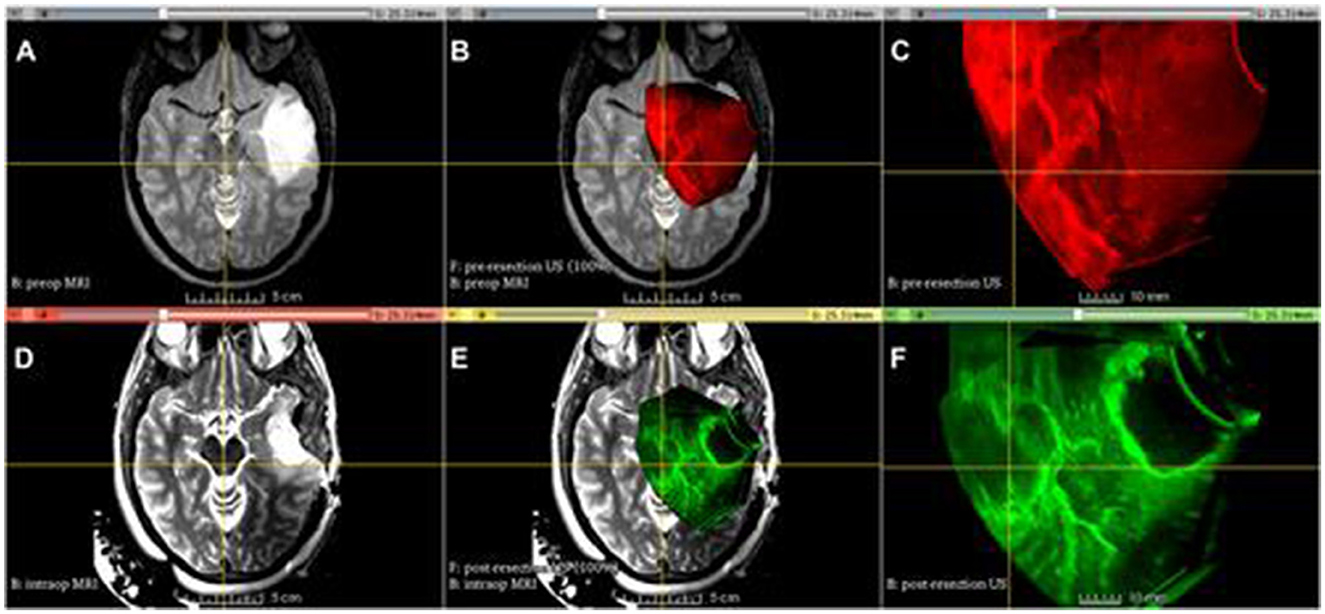

Brain scan images in a grid with six panels labeled A to F. Panels A, B, D, and E show MRI scans highlighting different brain regions. Panels C and F display ultrasonography images with red and green areas, indicating different levels of activity or tissue types. Each panel appears to represent different stages or techniques of imaging, possibly pre and post-procedure.

Figure 2. Advanced Multimodality Image Guided Operating (AMIGO) Suite at Brigham and Women's Hospital utilized tracked 3D US imaging and MRI during glioma resection. The following images show different images acquired during the procedure: (A) T2-fluid-attenuated inversion recovery (FLAIR) MRI before the operation, (B) 3D ultrasound before the durotomy, (C) 3D ultrasound before the durotomy, (D) 3D ultrasound before the durotomy, (E) 3D ultrasound during the operation, (F) 3D ultrasound after the initial tumor removal (29).

Comprehensive spatial reconstructions are generated by 3DUS by combining a coronal plane with typical two-dimensional (2D) imaging. This allows for the precise determination of tumor size, volume, and spatial orientation. Research has demonstrated that these skills enhance surgical results and reduce risks associated with difficult procedures, including vascular injury and persistent tumor tissue. There is a lot of evidence that 3DUS is useful in glioma surgery. As an illustration, 74% of patients had their health-related quality of life preserved during 3DUS-guided resections of low-grade gliomas (LGG) performed under general anesthesia, according to Bø et al. (127). Reaching gross total resection (GTR) in about 74% of cases, the extent of resection (EOR) was similar to those achieved with other modern neurosurgical techniques (30). The accuracy of 3DUS in estimating the area of resection was reported to be over 80% in a study of 162 brain tumor patients, including high-grade gliomas (HGG), LGG, and other diseases. The study demonstrated the versatility of the modality by showing how it safely contributed to procedural safety and precision while being sensitive in detecting tumor boundaries and for minimally invasive trajectories. The capacity of 3DUS to adapt in real-time to changes that occur during surgery, such as brain shift, because of things like tumor removal and cerebrospinal fluid (CSF) drainage, is one of its most notable features. Conventional navigation systems that depend on preoperative imaging frequently make navigational mistakes since they don't take these modifications into consideration (31). On the other hand, 3DUS offers real-time imaging updates, so surgeons always have accurate anatomical data to work with. The use of 3D ultrasound in awake procedures for eloquent LGGs was shown by Šteno et al. (32) to greatly increase the amount of tissue that could be removed, leading to an impressive 86.79% GTR rate when compared to traditional neuronavigation methods. The fact that this method was effective and safe in high-stakes surgeries without increasing the occurrence of long-term neurological impairments is crucial. The use of contrast-enhanced ultrasound (3D-CEUS), which uses microbubble contrast agents to increase the visibility of vascular systems and tumor edges, is another breakthrough linked with 3DUS. Because tumor vascularity frequently makes excision more difficult in high-grade glioma procedures, this method is very helpful in those cases. The use of 3D-CEUS increased imaging quality in more than half of the cases, as shown by Arlt et al. (33), who found that 90% of HGGs exhibit strong contrast uptake. Finding remaining tumor tissue intraoperatively and differentiating glioblastoma borders were both demonstrated by the study's authors as benefits of 3D-CEUS. Because 3D-CEUS provides imaging quality similar to postoperative MRI, it is a dependable tool for real-time resection control, and this integration has also been successful in reducing the risk of incomplete resections (3436). The usability of 3DUS is further enhanced by the integration of quantitative measures such as standard deviation (SD) and mean pixel brightness (MPB). With these measures, tumor echogenicity, heterogeneity, and infiltration can be objectively evaluated. According to Camp et al. (37), solid tumor components are linked to high MPB values, whereas necrotic cores and infiltrative margins are related with low MPB values. However, SD values show where the tumor and its borders have different levels of cellularity, thus they can help with surgical plane design and provide real-time insights into how the tumor is behaving. Recognizing any remaining tumor tissue during resection is an important step in achieving a more thorough excision and decreasing the likelihood of recurrence; these objective assessments are very helpful for this purpose. Although 3DUS has many benefits, it does have certain drawbacks (38, 39). Especially in cases of deep-seated cancers or intricate anatomical locations, image quality is crucial. Because understanding volumetric data necessitates competence in neuroanatomy and ultrasound principles, operator competence is crucial for optimizing the modality's potential. Even though 3DUS is more accessible and cheaper than IOMR, researchers are still working to improve its resolution and find ways to incorporate it with other imaging modalities such preoperative MRI and CT. According to Unsgaard et al. (40), this combined method is anticipated to generate extensive datasets using many modalities, which will allow for even more precise surgical procedures. To sum up, 3D ultrasound is a radical step forward in intraoperative imaging; it provides volumetric insights in real time, which improves surgical accuracy and patient outcomes. It is an essential tool for contemporary neurosurgery practice due to its versatility, low cost, and flexibility to integrate into existing surgical processes. 3D ultrasonic scanning (3DUS) has the potential to significantly impact the lives of patients dealing with complicated brain tumors if technology develops further. This includes higher resolution images, analysis powered by artificial intelligence, and hybrid imaging systems. There is mounting evidence that 3DUS is effective, thus it will continue to lead the way in intraoperative imaging innovations.